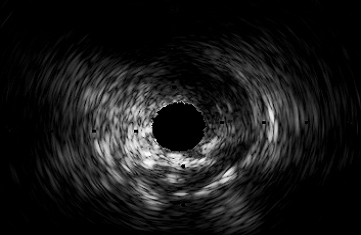

The local maxima of the stability score points to regions with high stability because the ratio of their current value to the change among their two neighbours is larger than the other surrounding elements. So, we select lumen and media from the detected local maxima. Specifically, a region with higher prominence value among the first two peaks is considered as lumen. If the IVUS image contains no artifacts, the media will be represented by the last detected peak. Based on our observation, the stability score of the images that contain serious artifacts have none or a small number of peaks since the presence of the artifacts interferes with the natural extraction of regions (see Figure 3(ii)). Therefore, when a small number of local maxima is detected, we consider the last extracted region as media. This process for an IVUS with no particular artifact is illustrated in Figure 3. The local maxima of the stability score indicates the regions for which the variation of the textural characteristics is more stable than their surrounding regions. As can be seen in Figure 3(i)(a), the second peak is selected as a suitable region for the lumen since it has a higher prominence than the first peak. Also, the region corresponding to the last peak of which is chosen as the media has been shown in Figure 3(i)(b).